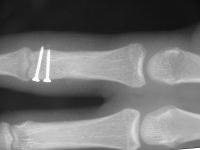

Unicondylar fractures of the phalangeal head are common, frequently unstable and unacceptably displaced. Although some may be treated successfully with percutaneous reduction and fixation, many require open reduction. In these cases, the screws were put right through the collateral ligament and sunk into the cortex. I think the simplest way to do this is to reduce and stabilize with two K wires, then remove the wires and replace with screws, one at a time, so reduction is maintained throughout. 1mm=39/1000" Kwire, so doing the math, here is how you choose the right sized Kwire to use as both drill and provisional fixation:

With two screws, bicortical fixation is not needed. The video below illustrates the steps involved, which are the same with either open or percutaneous fixation.